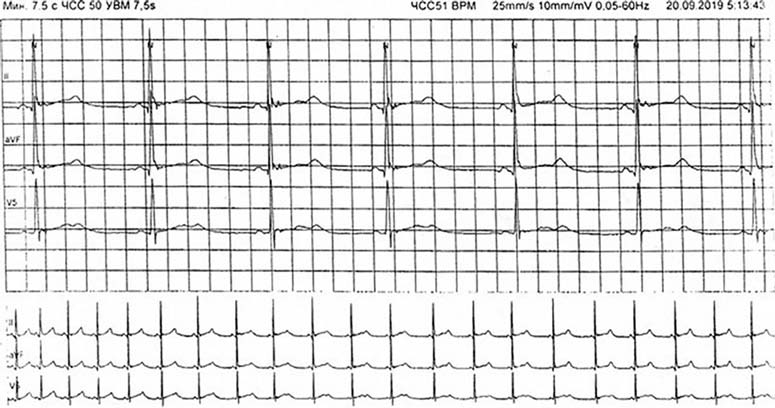

При холтеровском мониторировании ЭКГ от 19.09.2019 длительностью 22 ч 29 мин ритм синусовый, максимальная частота сердечных сокращений 166 в минуту, QT=289 мс, минимальная частота сердечных сокращений 50 в минуту, PQ=131 мс, QT=558 мс. Эктопическая активность не зарегистрирована. На всём протяжении исследования зарегистрирована альтернация зубца Т. Паттерн ранней реполяризации желудочков. Показатели вариабельности сердечного ритма в норме (рис. 1).

Рис. 1. Холтеровское мониторирование электрокардиограммы пациентки С. Альтернация зубца Т